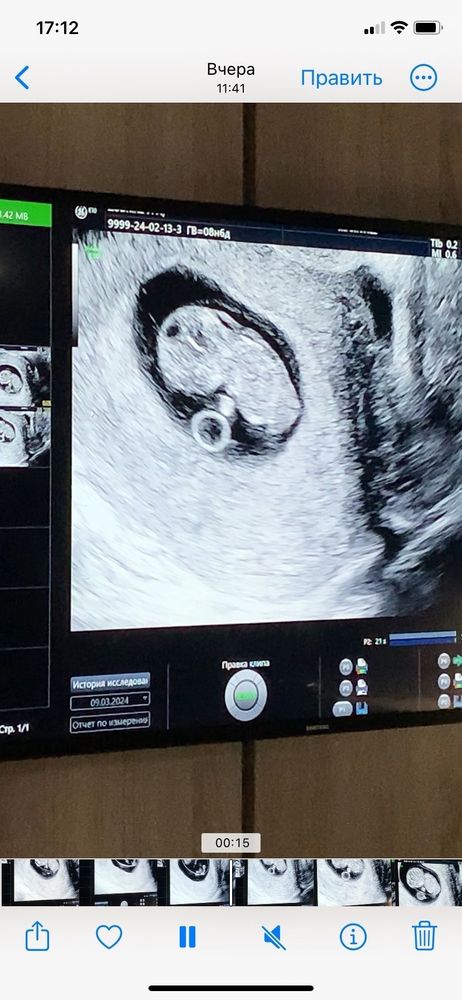

Узи 9 недель

Катерина , ой, я вообще без понятия 😄 Она сказала, что развивается хорошо, отслоек нет. Потом зачем - то навела на воротниковое пространство, сказала про него, но что увеличено не сказала. Сказала мол, что лучше бы пораньше скрининг сделать, на 12-13 неделе, чтобы посмотреть на наличие к ХА, вот так вот) Может я её не так поняла, но мне показалось, что что - то не так по её виду и выражению лица. Врач хорошая, главный врач в этой платной клинике, поэтому и расстроилась как - то. Сейчас у меня уже срок 9.4, а то узи было сделано в 8.6, так и хочется ещё раз на узи сходить до скрининга 😁 Не могу, нервничаю слишком из-за этого

Там же вообще еще крошка какой твп мерить,у меня был такой же карапуз на 9 неделе.В 12+5 по скринингу твп 1,5 и все шикарно.Вам рано разводить панику,дождитесь скрининга 🥰

Рано ещё для данного показателя. Дождитесь скрининга)))все хорошо с вашим мальчонком( по поводу пола чисто мои предложения по данным фото)